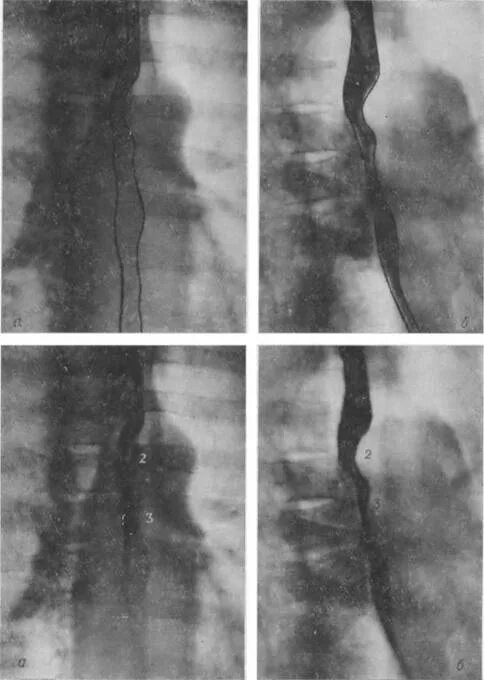

Стеноз пищевода симптомы